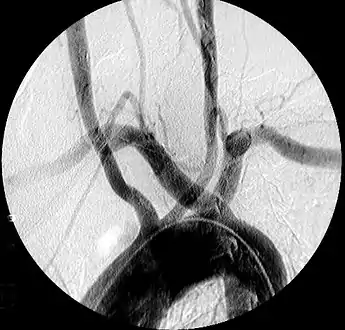

Aberrant subclavian artery on MR angiography.

Aberrant subclavian artery is a rare anatomical variant of the origin of the right or left subclavian artery. It is the most common congenital vascular anomaly of the aortic arch,[1] occurring in approximately 1% of individuals.[1][2][3]

This condition is usually asymptomatic.[1] The aberrant artery usually arises just distal to the left subclavian artery and crosses in the posterior part of the mediastinum on its way to the right upper extremity.[2] In 80% of individuals it crosses behind the esophagus.[2] Such course of this aberrant vessel may cause a vascular ring around the trachea and esophagus. Dysphagia due to an aberrant right subclavian artery is termed dysphagia lusoria, although this is a rare complication.[2][3] In addition to dysphagia, aberrant right subclavian artery may cause stridor, dyspnoea, chest pain, or fever.[1] An aberrant right subclavian artery may compress the recurrent laryngeal nerve causing a palsy of that nerve, which is termed Ortner's syndrome.[4]

The aberrant right subclavian artery frequently arises from a dilated segment of the proximal descending aorta, the so-called Diverticulum of Kommerell (which was named for the German radiologist Burkhard Friedrich Kommerell (1901–1990), who discovered it in 1936).[5][6] It is alternatively known as a lusorian artery.[1][3]

The evaluation of an aberrant subclavian artery can be done via CT angiography[7], which is a combo of CT scan with an injection of dye to produce images of blood vessels and/or tissues [8]